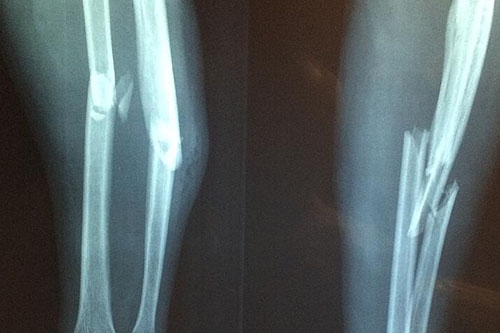

梦见自己是小腿断了是什么意思

梦见自己是小腿断了是什么意思?